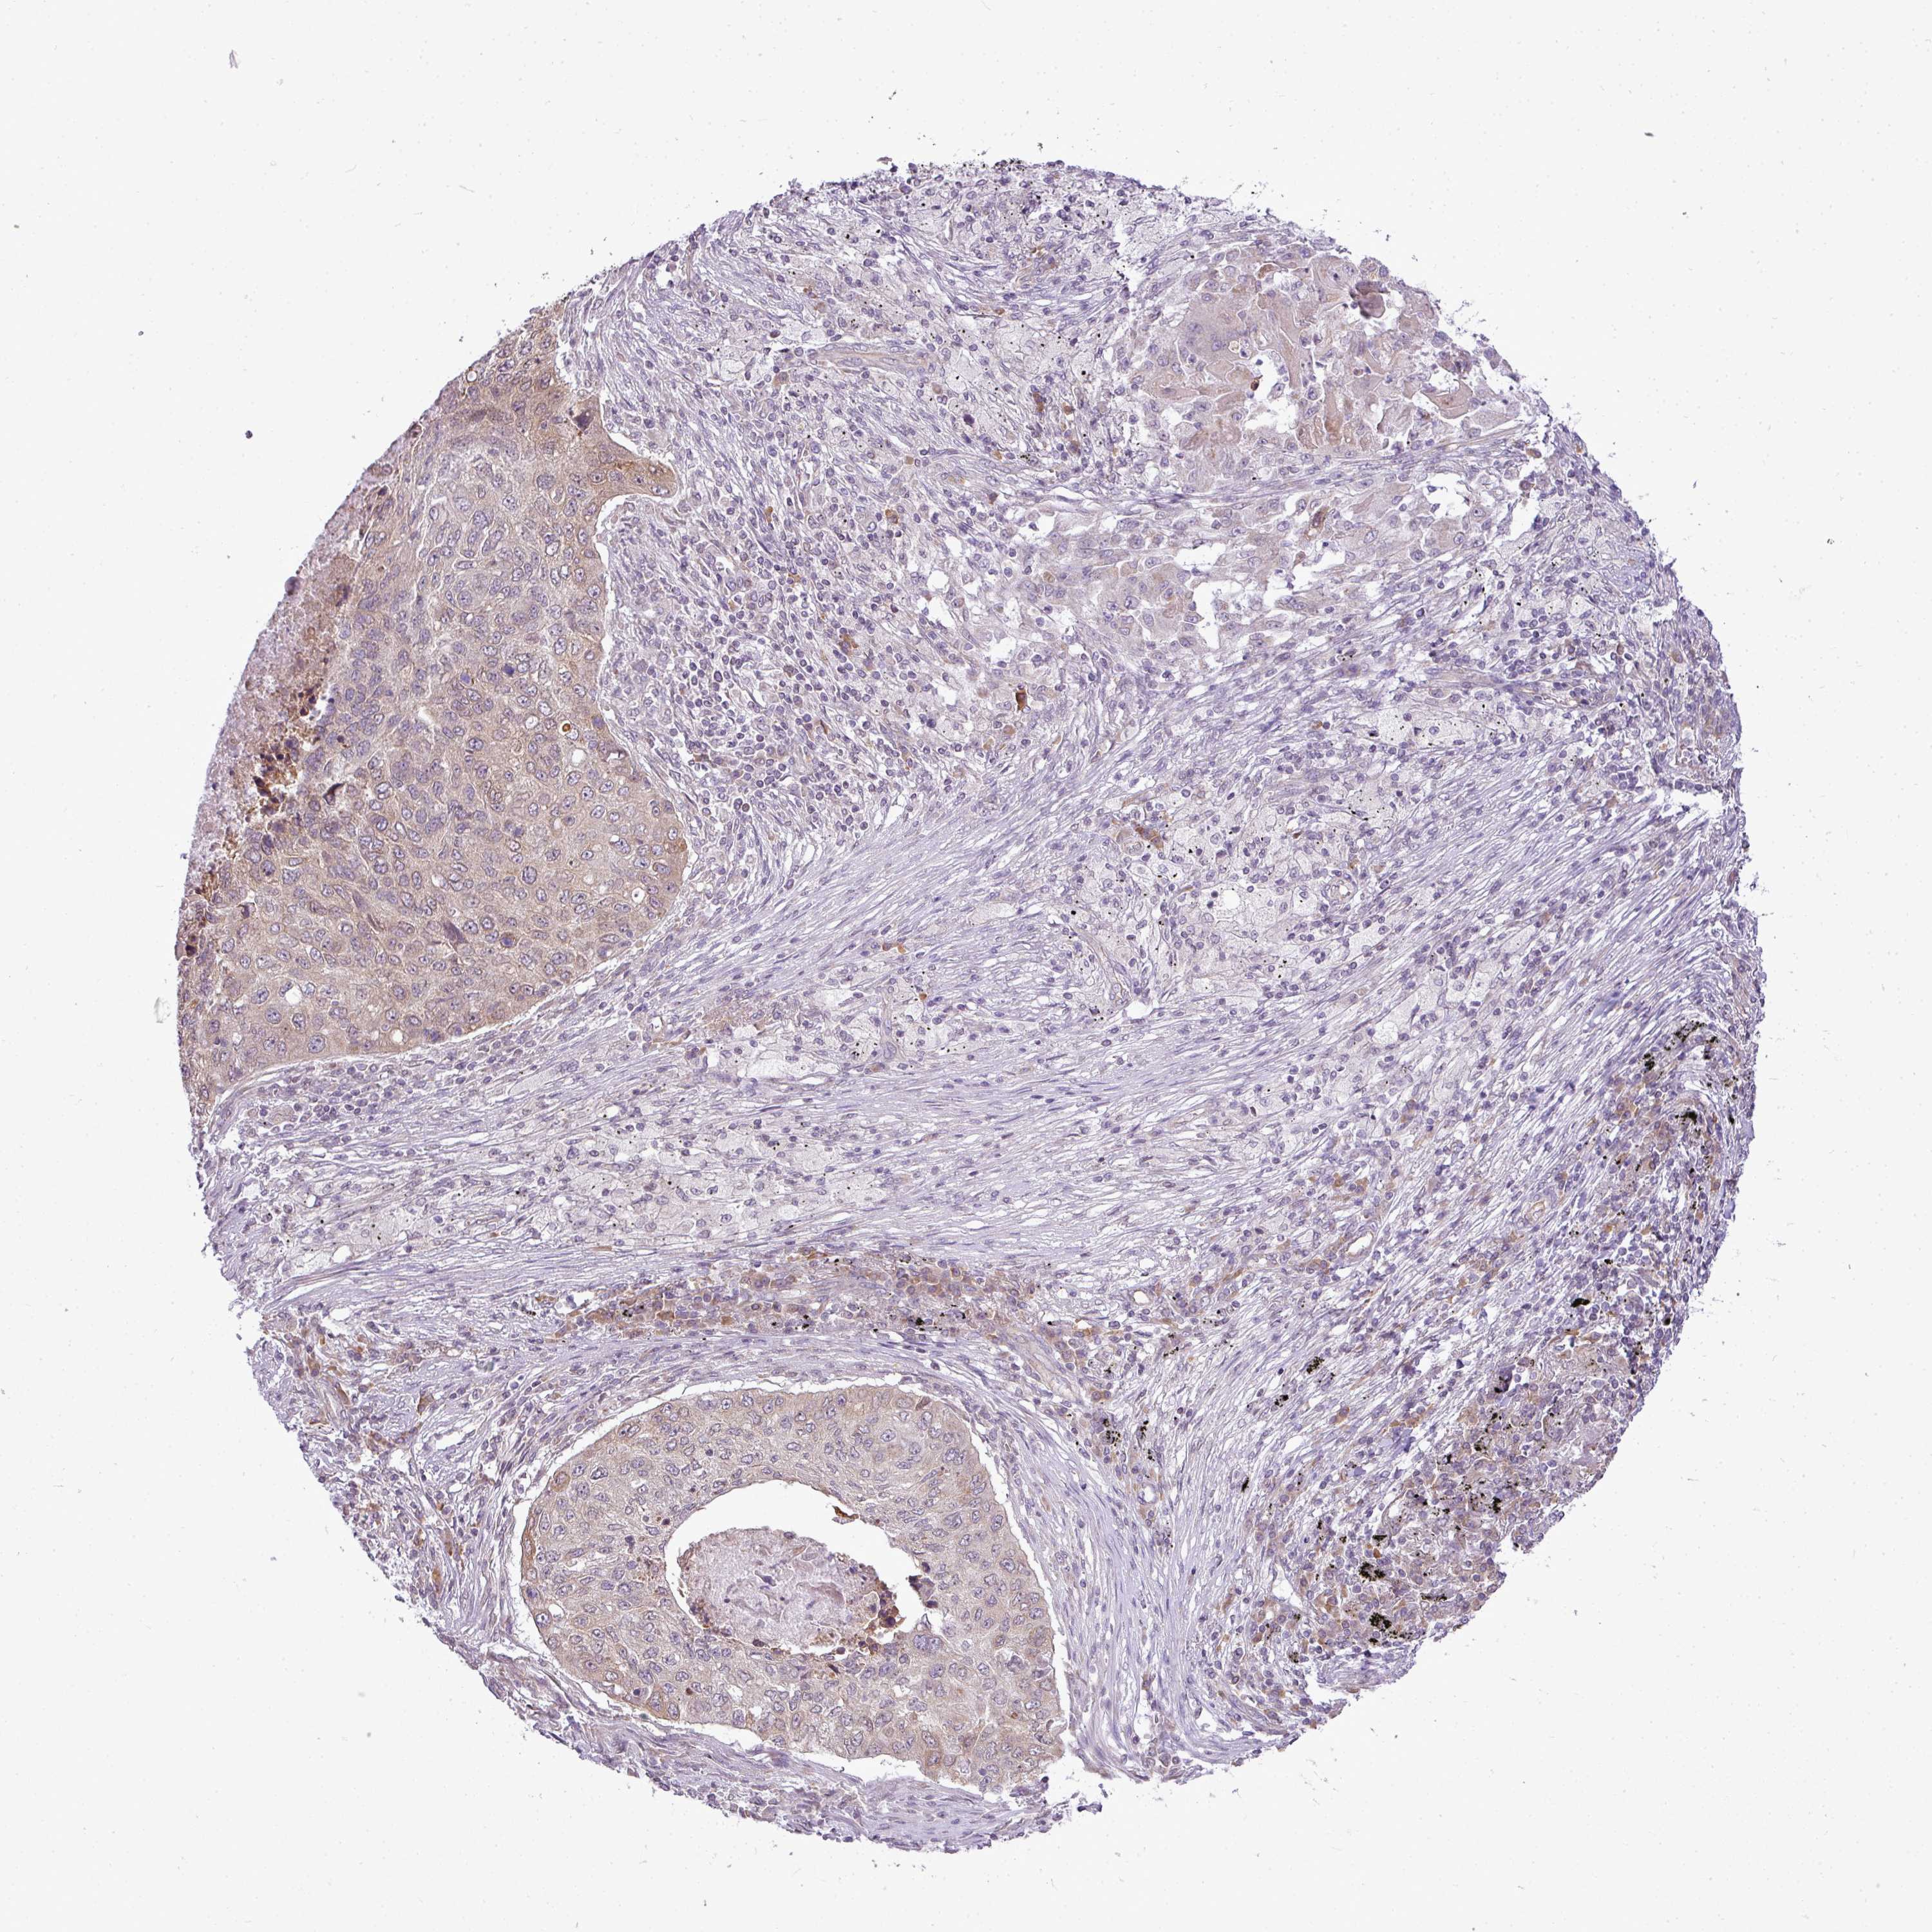

CANCER LUNG CANCER Show tissue menu

LUAD TCGA LUAD VALIDATION LUSC TCGA LUSC VALIDATION PROTEIN LUAD CPTAC PROTEIN LUSC CPTAC PROTEIN EXPRESSION